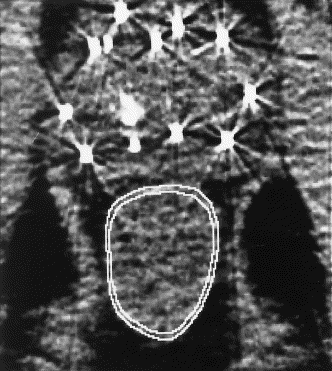

countouring for the surface area converting rectal surface area to DVH of  the rectum

The rectal postimplant dosimetry was calculated from a CT scan obtained 4–6 weeks after implantation using software developed in-house. For this purpose, the rectum was defined as the portion of the rectum between the base and the apex of the prostate (i.e., the rectum was only contoured on CT images that contained prostate).